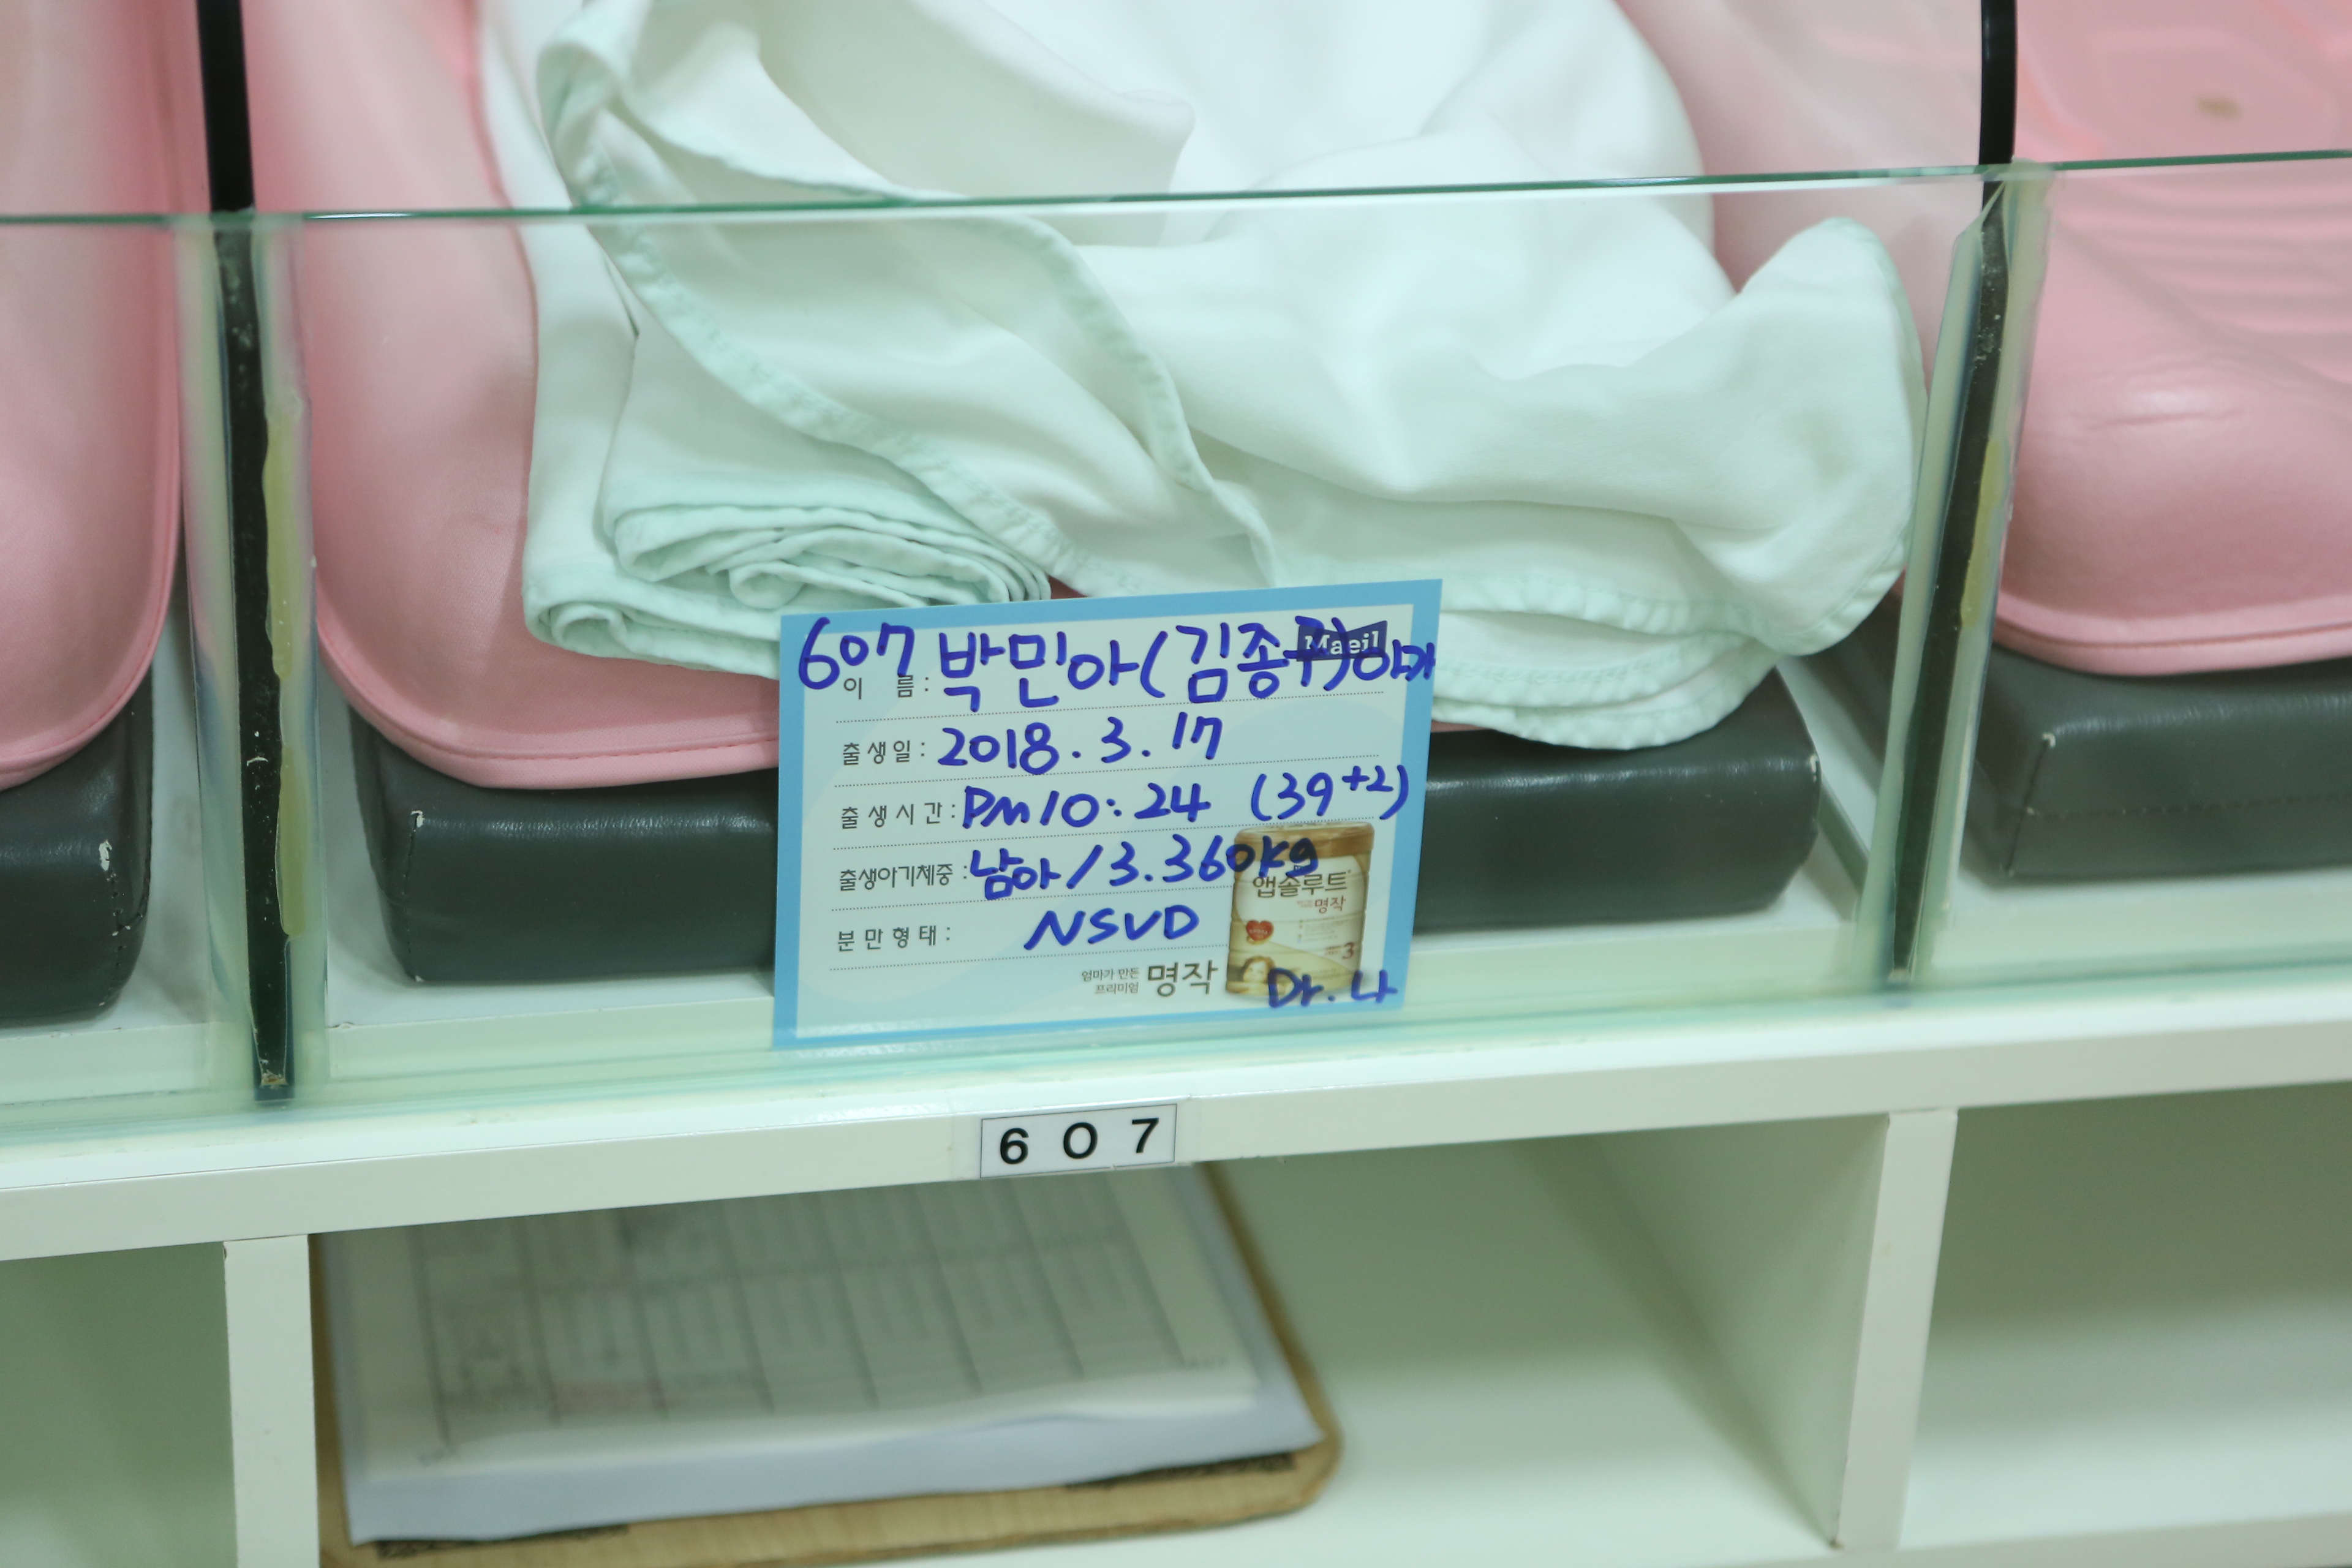

2018년 4월 27일 신생아실과 산후조리원의 예성이 본문